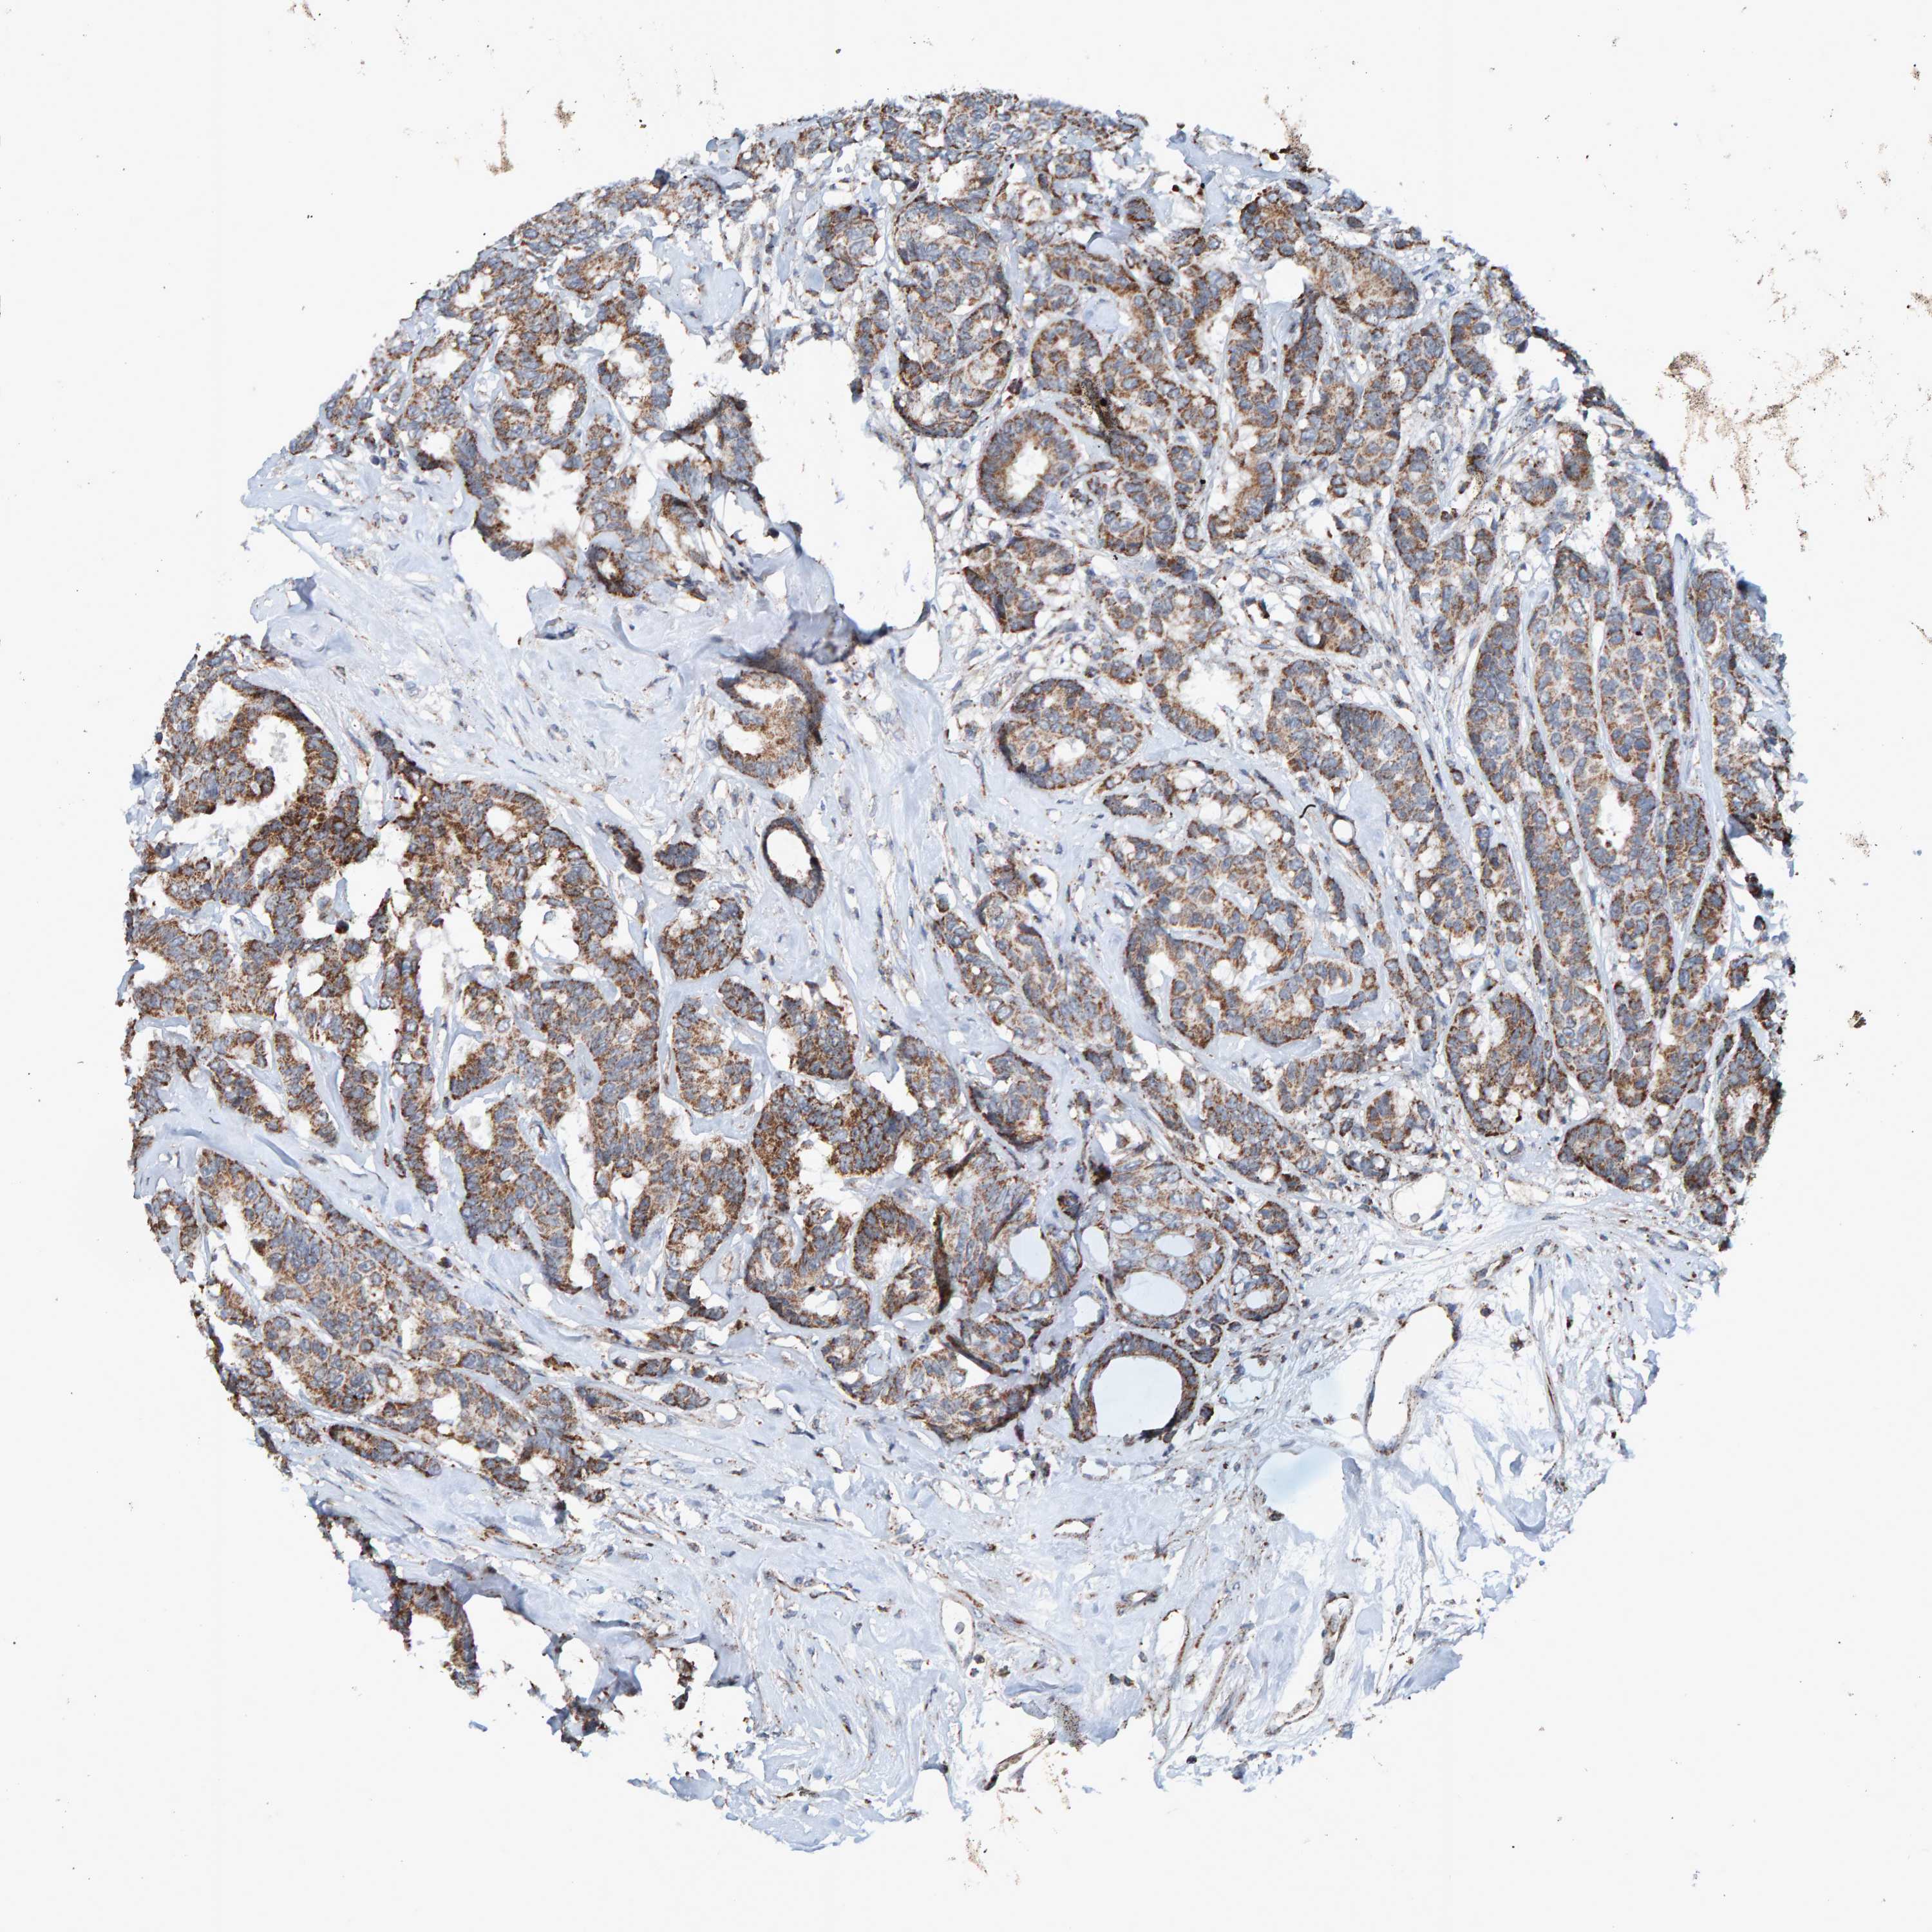

CANCER BREAST CANCER Show tissue menu

BRCA TCGA BRCA VALIDATION PROTEIN EXPRESSION